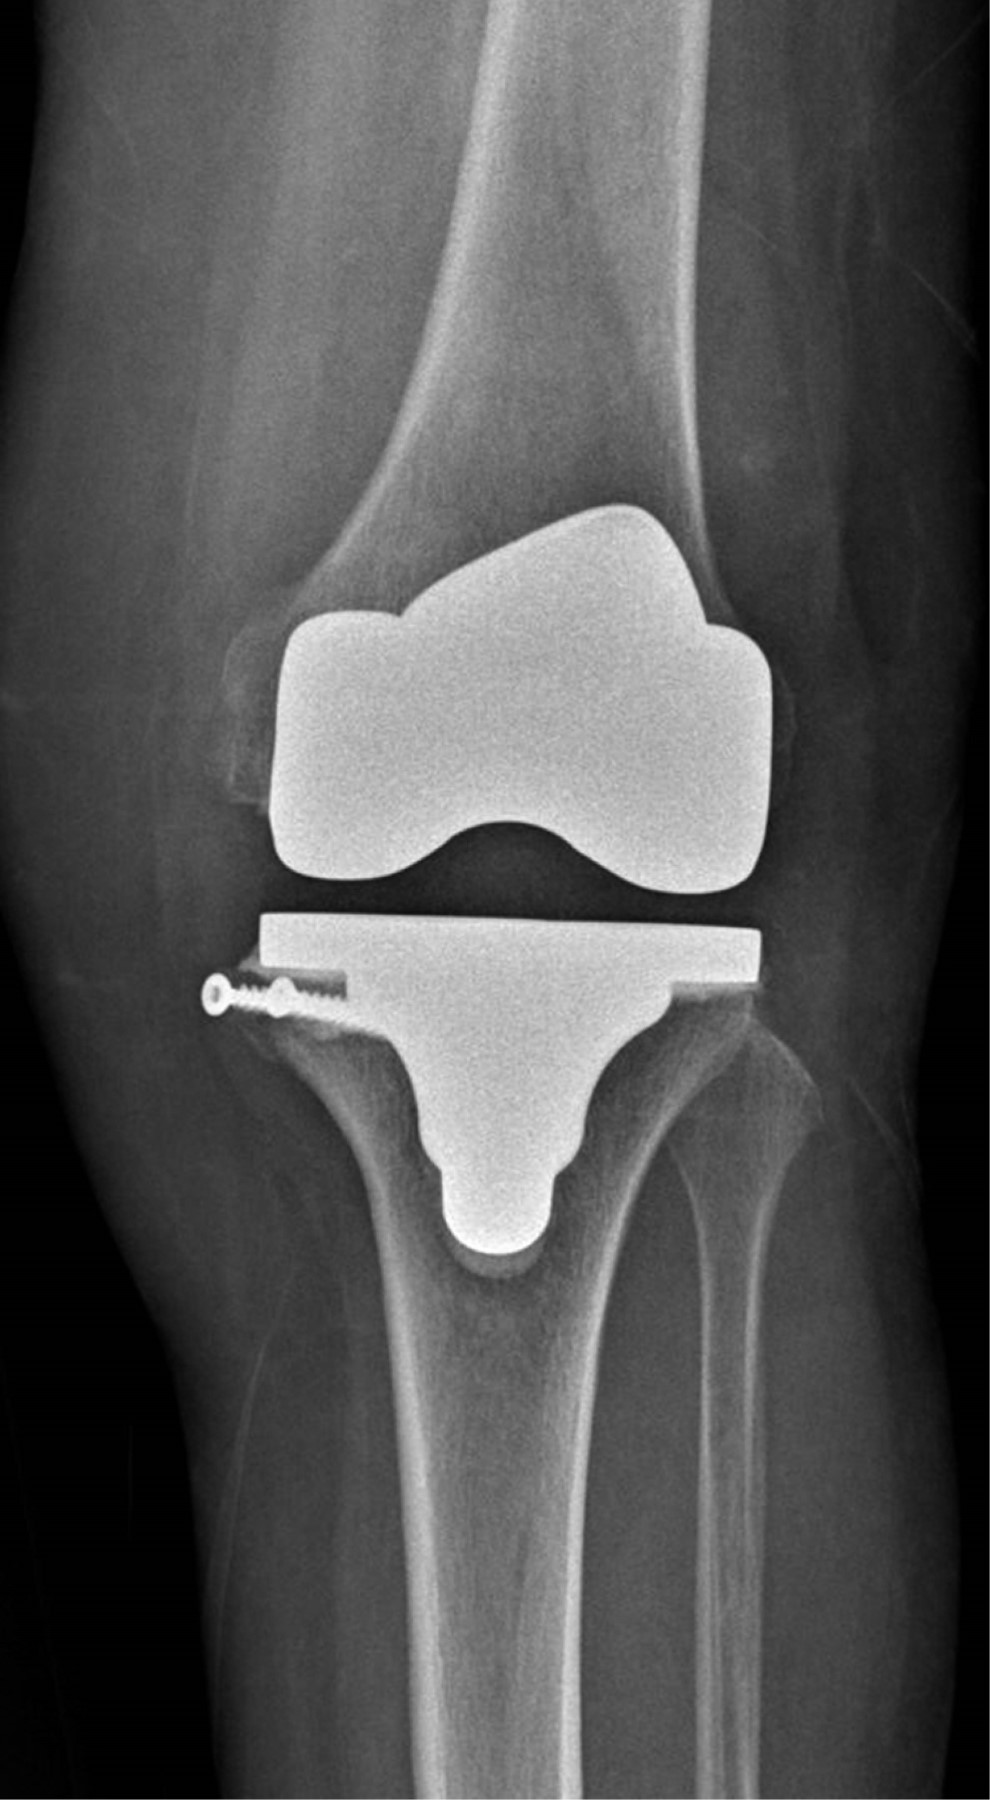

Se presenta caso de mujer de 62 años, dedicada al cuidado del hogar, con antecedente de presbiacusia, la cual acude a consulta externa por gonalgia bilateral, de predominio izquierdo, de siete años de evolución. A la exploración física se aprecia franca deformidad en varo en ambas rodillas (Figura 1), de mayor magnitud en lado izquierdo, con marcha independiente asistida con bastón, rango de movilidad activo con extensión de -5o, flexión de 85o, Ficat y cepillos positivos, cajones negativos y bostezo medial positivo, con limitación por dolor para las actividades de la vida diaria y dolor en EVA de 8. Se solicitan y revisan radiografías anteroposterior (Figura 2) y lateral (Figura 3) de ambas rodillas en bipedestación, encontrando gonartrosis bilateral Kellgreen & Lawrence IV, con defecto tibial medial en rodilla izquierda, por lo cual se le propone tratamiento quirúrgico con artroplastia total de rodilla izquierda posteroestabilizada, debido a la mayor sintomatología en dicho lado.

Figura 1

Figura 2